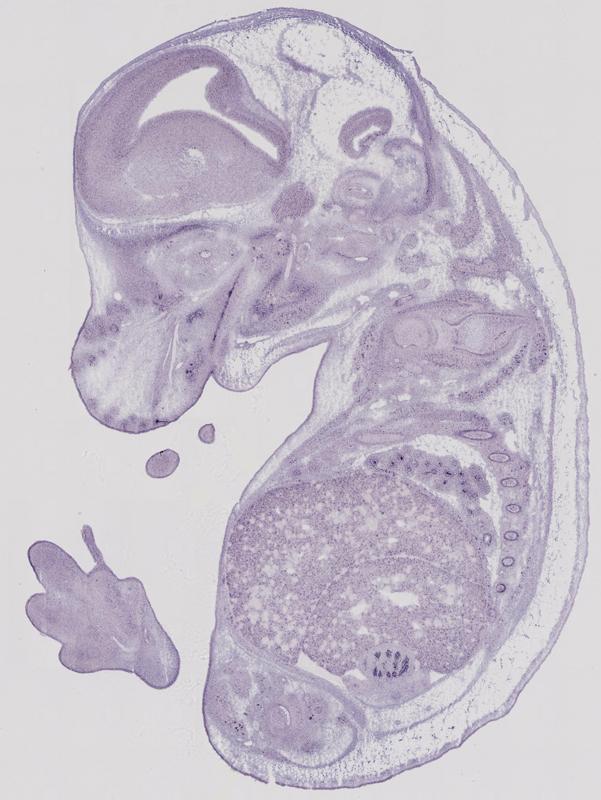

euxassay_008180_06:

embryonic day 14.5

euxassay_008180_07:

Specimen

euxassay_008180_08:

euxassay_008180_20:

euxassay_008180_21: